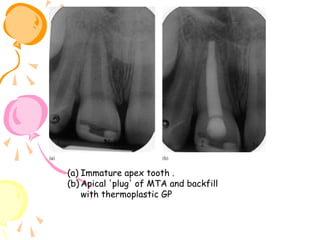

Pulp amputation (apexogenesis procedure)

.of a permanent incisor

a)Complicated fracture of an immature )

incisor with microbial invasion of the

coronal pulp. The pulp has been exposed to

.the mouth for more than 24 h

b) Access to the coronal pulp and )

amputation of coronal pulp tissue with a

diamond bur running at high speed with

.constant water cooling

c) Dressing the pulpal wound to promote )

calcific repair. Non-setting calcium

hydroxide cement is flowed on to the pulp,

then overlaid with a hard cement, and the

.tooth restored with composite resin

d) The same tooth after 12 months )

showing calcific barrier formation. The

calcific barrier was directly inspected in

this case, (not always required), and a new

layer of setting calcium hydroxide cement

placed on the barrier before definitive

restoration. The remaining pulp has stayed

healthy and deposited dentine to complete

.root formation